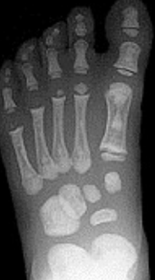

What disease is this? | Rheumatoid arthritis |